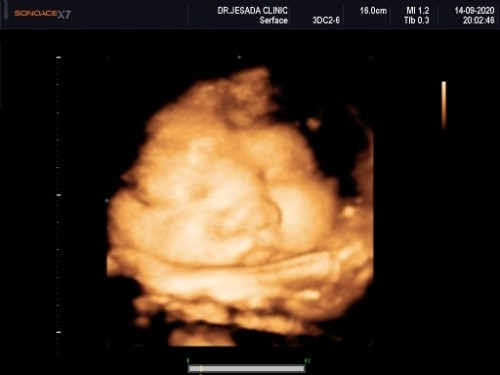

มาอวดรูปตอนซาวด์กันหน่อยค่ะ แม่ๆกำหนดคลอดเดือนไหนบ้างคะ